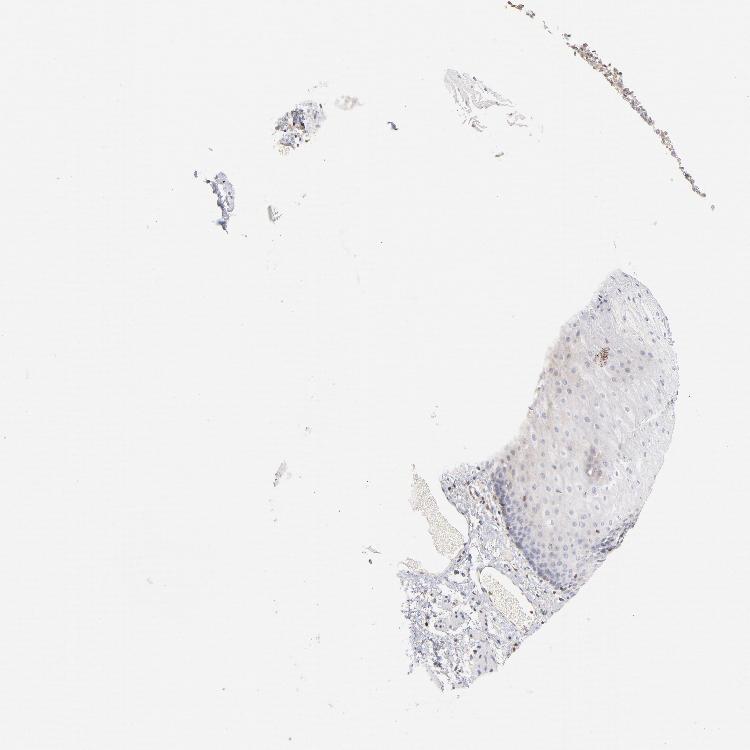

ESOPHAGUS - Antibody stainingi

Antibody staining in the annotated cell types in the current human tissue is reported as not detected, low, medium, or high, based on conventional immunohistochemistry profiling in selected tissues. This score is based on the combination of the staining intensity and fraction of stained cells.

Each image is clickable and will lead to virtual microscopy that enables deeper exploration of all samples and also displays staining intensity scores, fraction scores and subcellular localization as well as patient and tissue information for each sample.

Antibody HPA003739Antibody CAB009737

Squamous epithelial cells Not detectedNot detected